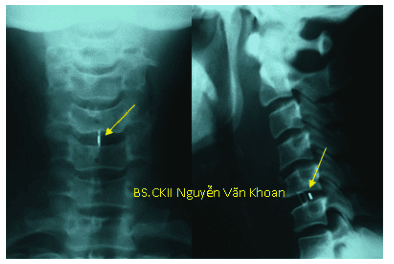

4.1 Chụp X quang

Giúp đánh giá đường cong sinh lý cột sống, có thể thấy được các gai xương thoái hóa, hẹp đĩa đệm, hẹp lỗ liên hợp.

Phẫu thuật cắt đĩa C5/C6 giải ép, đặc nêm PEEK lối trước. Sau mổ bệnh nhân hết đau, trở lại sinh hoạt bình thường sau 2 tháng.